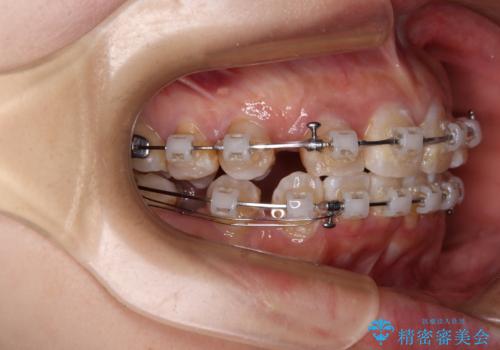

- 矯正装置

- 審美装置

- 上下前歯のデコボコを気にして来院された患者様です。

上顎は両側の犬歯が骨内に埋伏しており、乳歯が残存している状態でした。

歯肉内に埋もれている場合には牽引することも可能ですが、両歯ともに骨内に完全に埋もれていたため、牽引することは不可能と判断しました。

口元の突出感があるわけではなく、叢生の程度もシビアではありませんでしたが、顎骨が小さく、左右ともに最後臼歯が歯肉に埋もれているため、下顎は左右第二小臼歯を抜歯することとしました。

上顎は左右ともに残存している乳歯を抜歯し、上下歯列を整えることとしました。

下顎は第二小臼歯を抜歯したため、治療期間が長期化すると思われましたが、大臼歯が後方に傾斜していたため、容易にスペースを閉じることができ、2年強で治療を終えることができました。